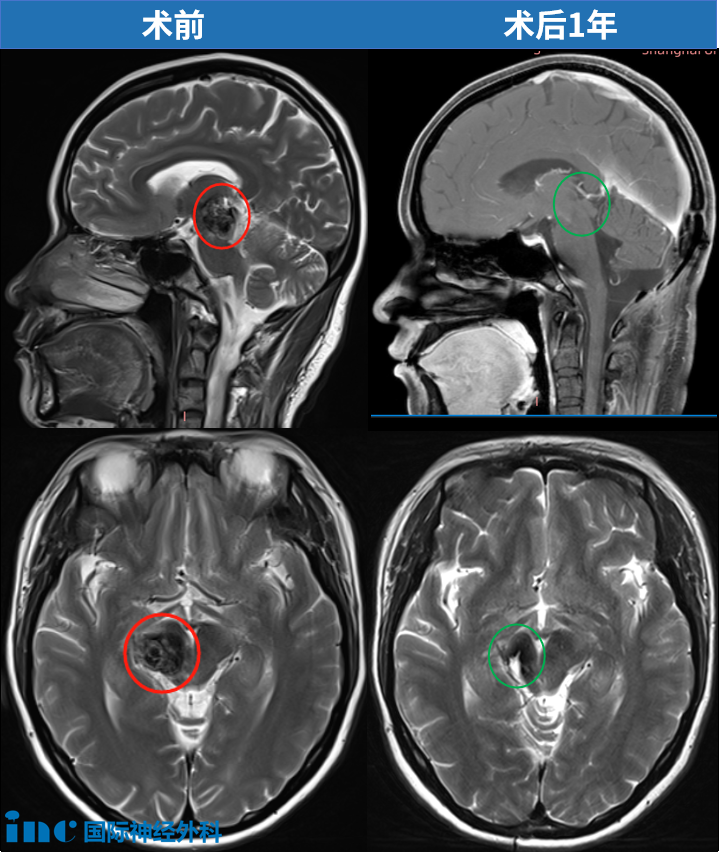

思睿于2018年因丘脑出血出现复视、记忆障碍及左侧偏瘫。初次出血后选择保守治疗,第二次出血后卧床不起。巴教授成功为其全切丘脑-中脑海绵状血管瘤,术后第一天四肢功能恢复正常,一年后随访显示肿瘤完全切除,临床状态恢复良好。

点击阅读:37岁妈妈历时7年战胜“手术禁区”脑干肿瘤,坚持的力量强的没边了!